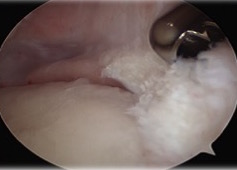

Pass graft

- place suture at junction of body and posterior horn

- make posteromedial approach

- insert graft bone into slot

- secure with screw

- flip meniscus

- secure posterior horn with all inside sutures, body with inside out, anterior horn with outside in